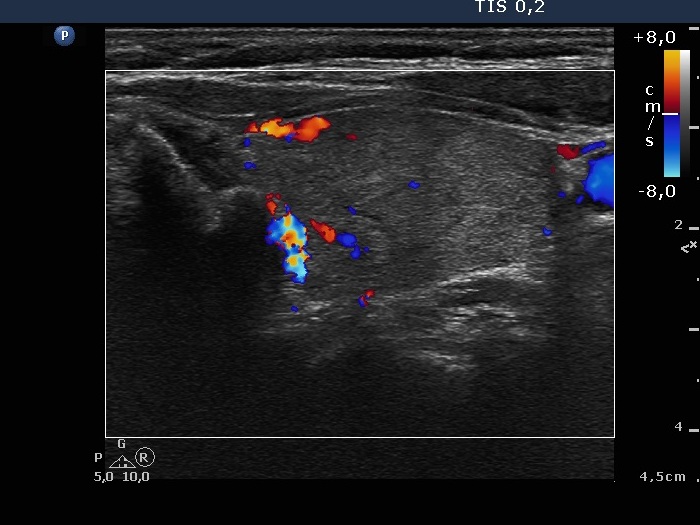

Right lobe, longitudinal scan

Upper part of the left lobe, transverse scan, color Doppler mode. The vascularization is not specific.